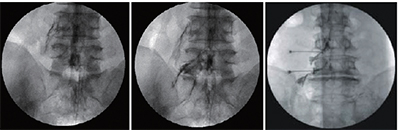

신경 성형술

1mm의 초소형 카테터를 삽입하여 통증의 원인이 되는 부위를 찾아 신경 유착을 풀어주는 시술로 가장 대중적으로 사용되어지고 있는 척추질환 비수술치료 입니다.